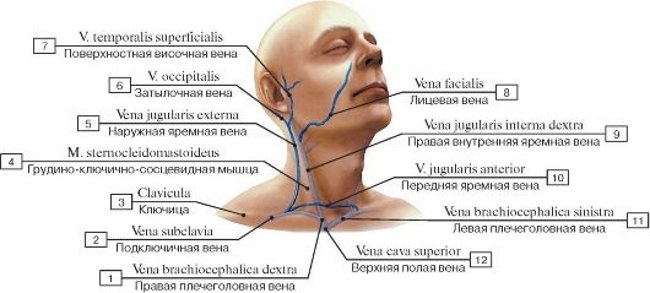

Анатомия внутренней яремной вены: КТ изображения